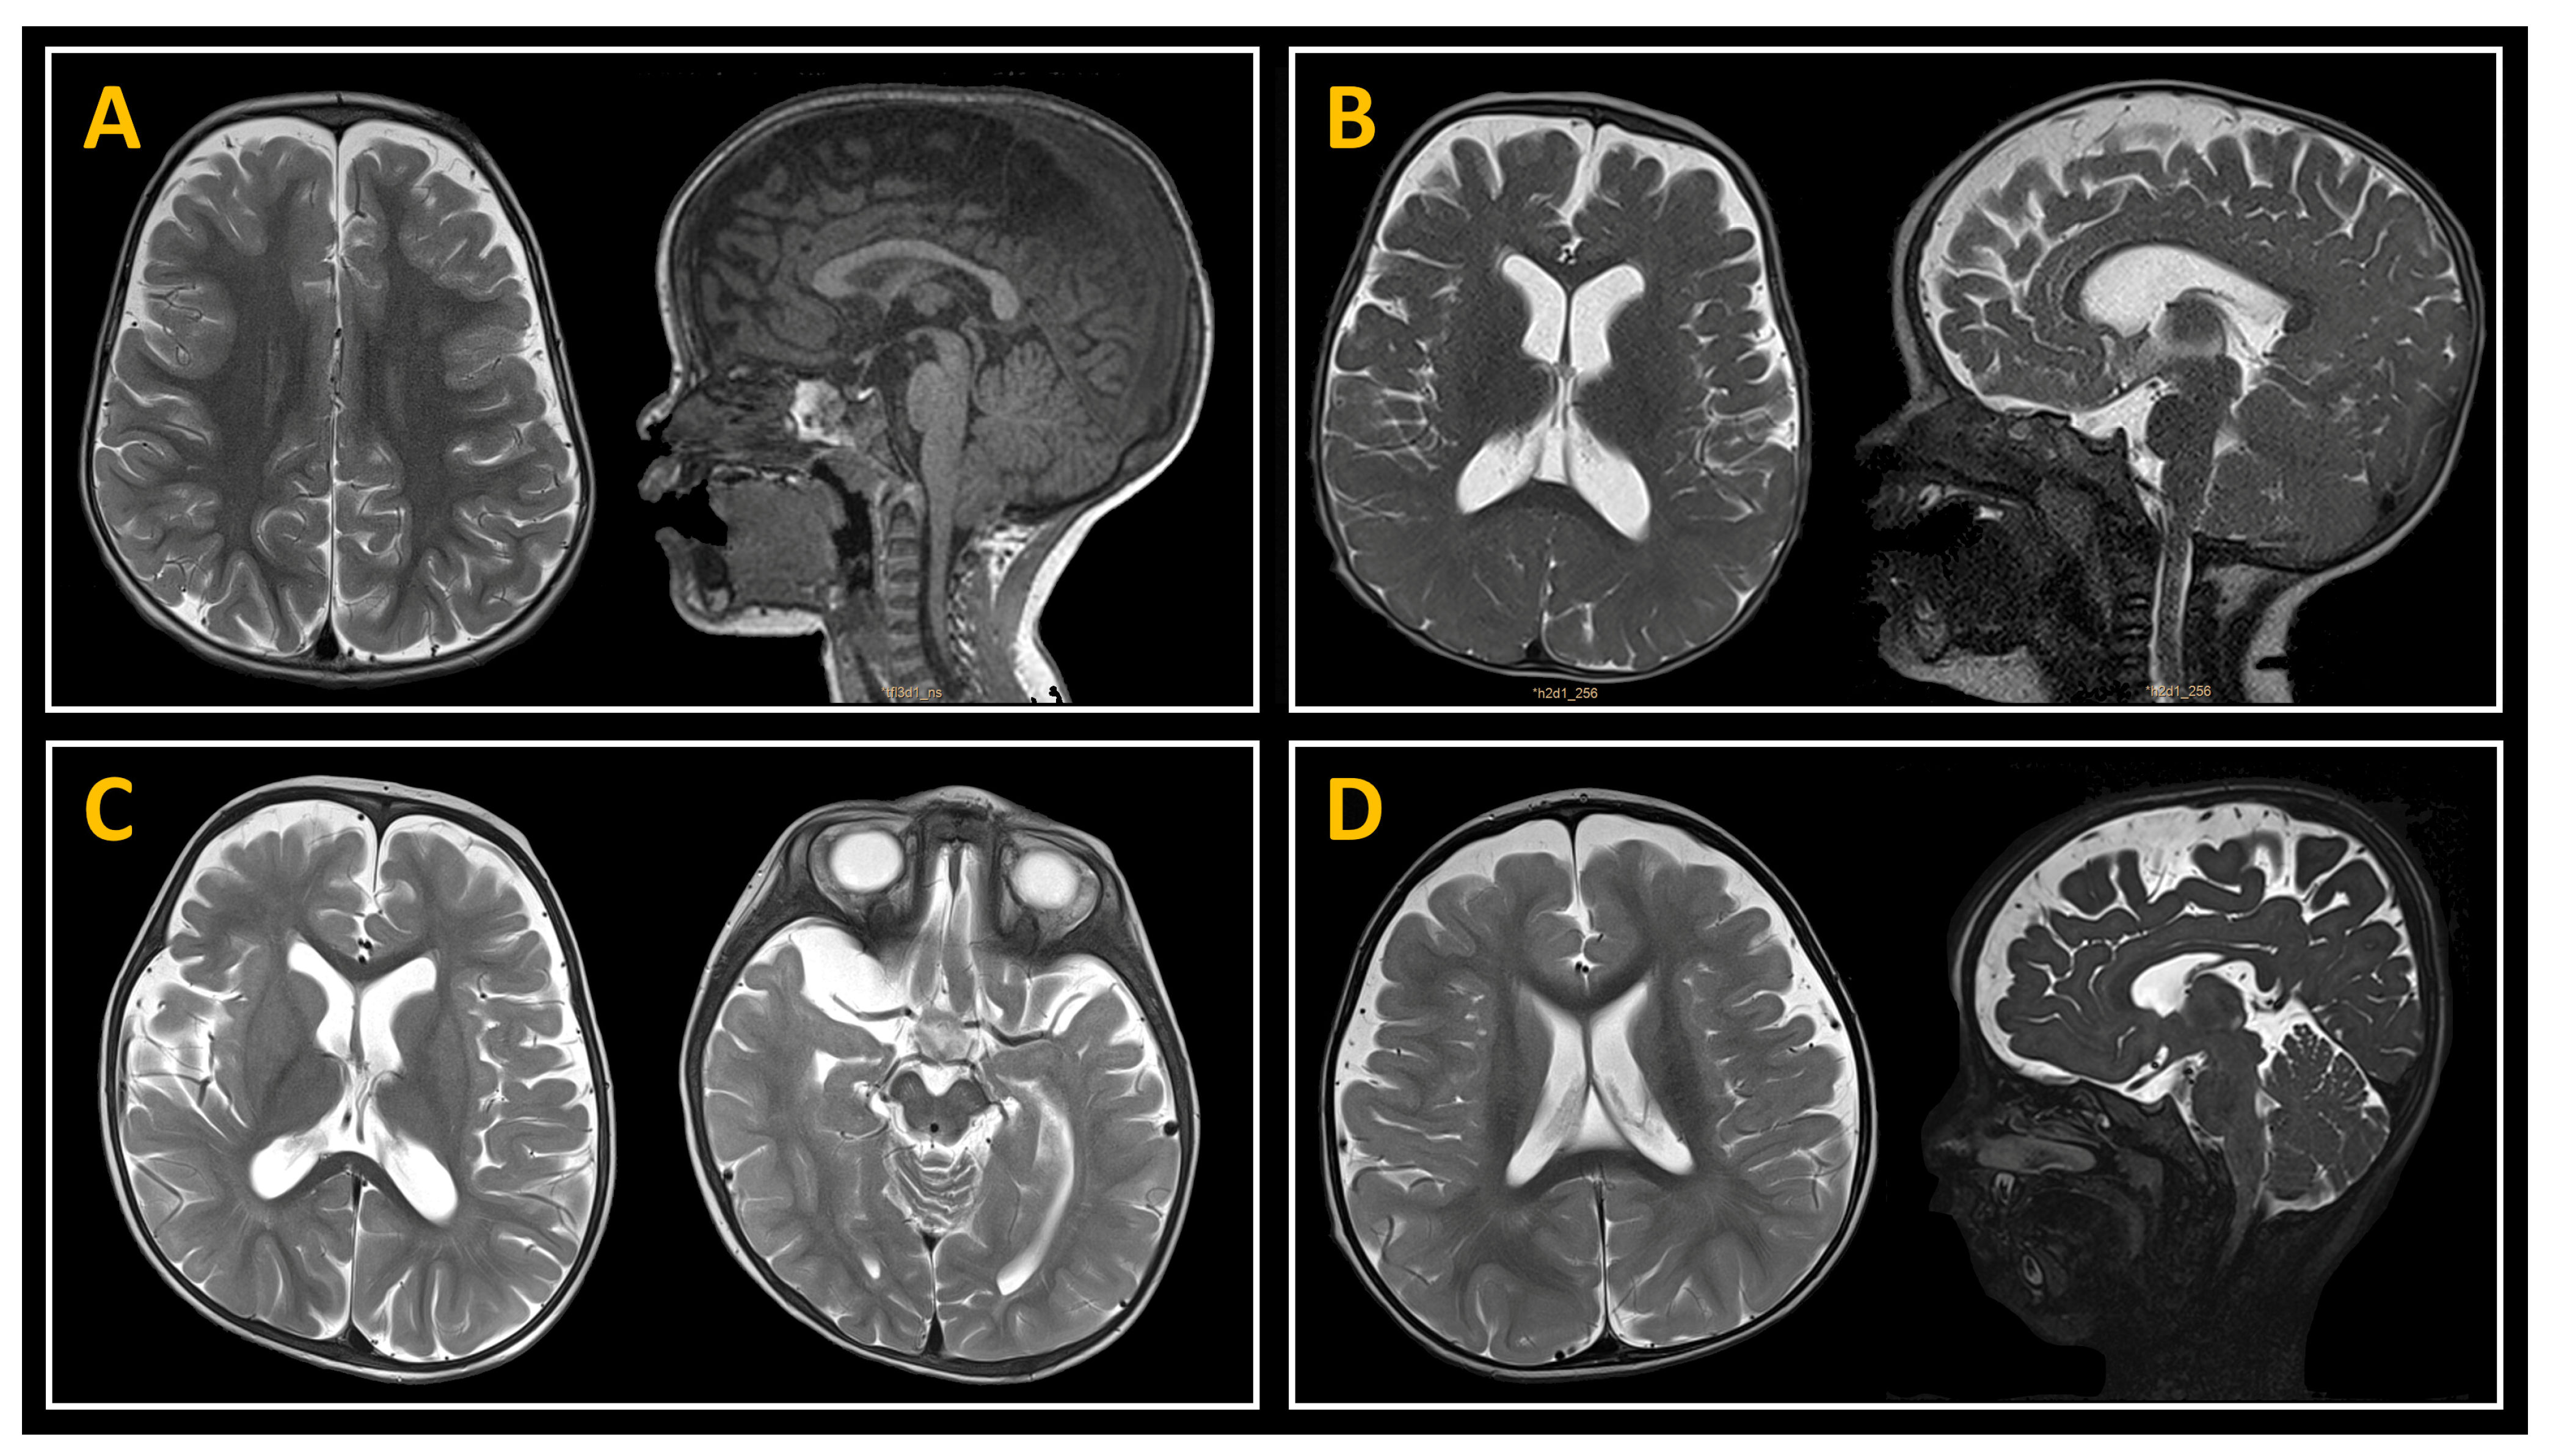

2.3. Neuroimaging Studies

3.2. Neuroimaging Data